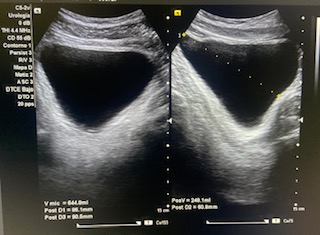

Vejiga bien repleccionada sin alteraciones a simple vista.

Volumen residual: 243 ml. Próstata de contornos regulares y ecogenicidad homogénea a simple vista. Volumen prostático: 49 cc.

En ecografía determinamos el tamaño de la próstata mayor de 20 cc, por tanto se trata de una HBP grado II. La medición del RPM nos permitió detectar que el paciente presentaba residuos elevados (243 ml).

Nueva ecografía de control en seis meses se recomienda segunda determinación dada la variabilidad de la prueba en el estudio de RPM y control clínico de STIU a pesar del tratamiento.